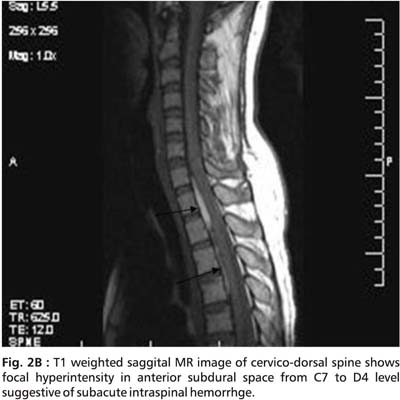

An initial MRI cervical spine revealed cervical cord edema at C5 to C7 ( Fig.1). A repeat MRI done after 15 days showed striking changes in the same area (Fig. 2A, 2B, 2C and 2D).

The cervical MR findings are suggestive of subacute spinal subdural hemorrhage appearing hyperintense on both T1 and T2 images. Serpigenous flow voids were seen on axial sections suggestive of Arterio-Venous malformation (AVM). Unfortunately, a subsequent angiographic study could not be done.